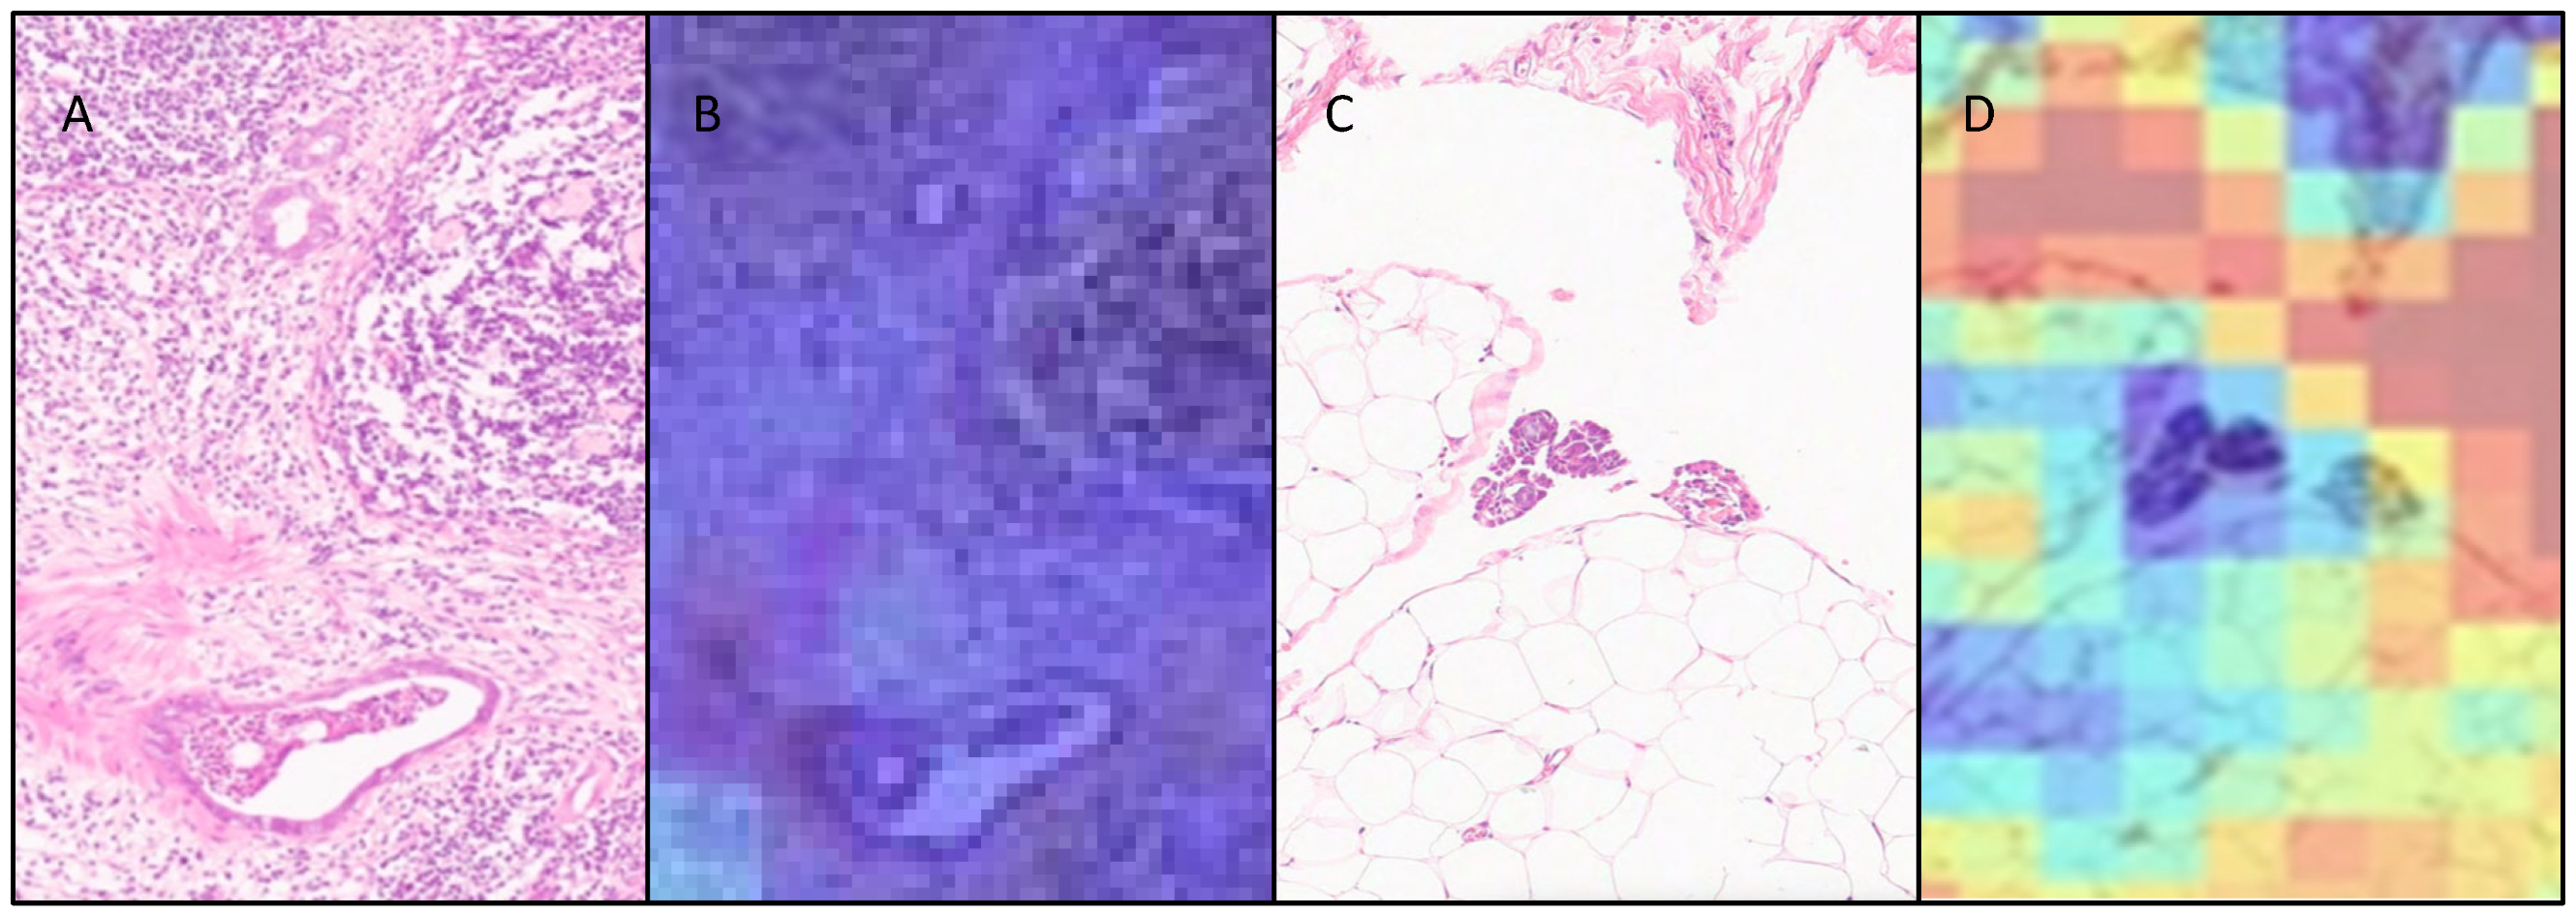

3.3. Attention Heatmaps